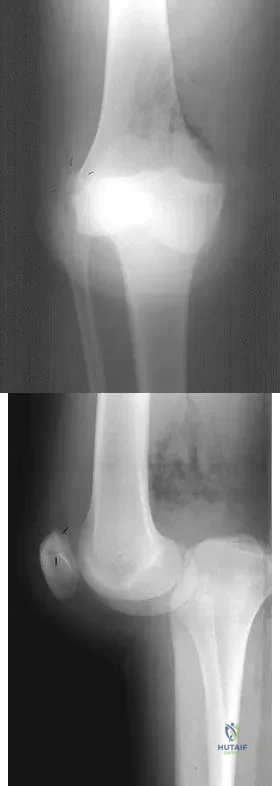

Figure 13 shows the radiographs of a 20-year-old intercollegiate basketball player who was injured 6 weeks prior to the start of the season. What is the most appropriate treatment?

Figure 1 shows the radiograph of an 18-year-old patient who has severe knee pain. Treatment consisting of osteotomy should be perfomed

Figures 28a and 28b show AP and lateral radiographs of the knee. Based on these findings, which of the following structures has most likely been injured?

A 23-year-old woman reports right knee pain and fullness. The pain is worse with activity but also present at rest. Radiographs are shown in Figures 20a and 20b. What is the most likely diagnosis?